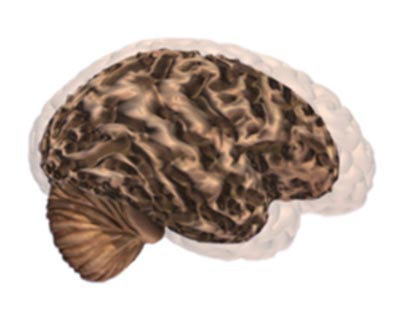

Alzheimer's disease leads to nerve cell death and tissue loss throughout the brain. Over time, the brain shrinks dramatically, affecting nearly all its functions.

These images show:

A brain without the disease.

A brain with advanced Alzheimer's.

How the two brains compare.

Severe Alzheimer's Disease

In advanced Alzheimer's disease, most of the cortex is seriously damaged. The brain shrinks dramatically due to widespread cell death. Individuals lose their ability to communicate, to recognize family and loved ones and to care for themselves.